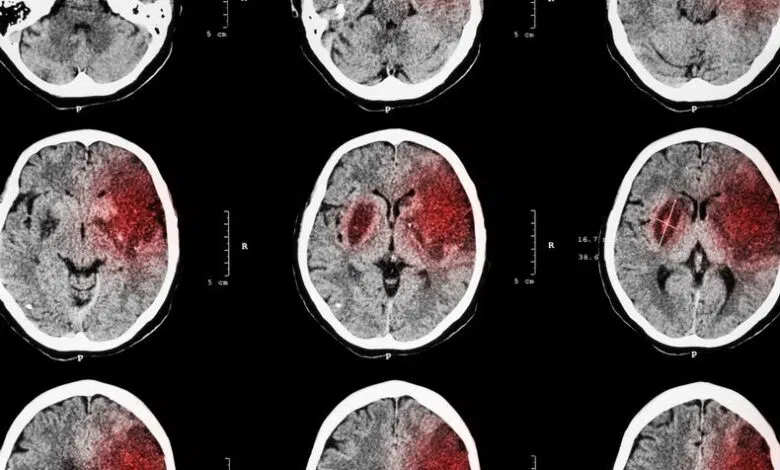

Apuntar a la inflamación protege y restaura el cerebro después de un accidente cerebrovascular

En un accidente cerebrovascular isquémico, un coágulo bloquea los vasos sanguíneos que van al cerebro, privando a algunos órganos críticos de oxígeno y nutrientes. Si no se trata de inmediato, esto puede provocar daños irreversibles en los tejidos, lo que lleva a complicaciones que van desde cambios de comportamiento hasta parálisis. El accidente cerebrovascular es la quinta causa principal de muerte en los Estados Unidos y la principal causa de discapacidad a largo plazo. El accidente cerebrovascular isquémico es el tipo más común y representa más del 80% de todos los casos.